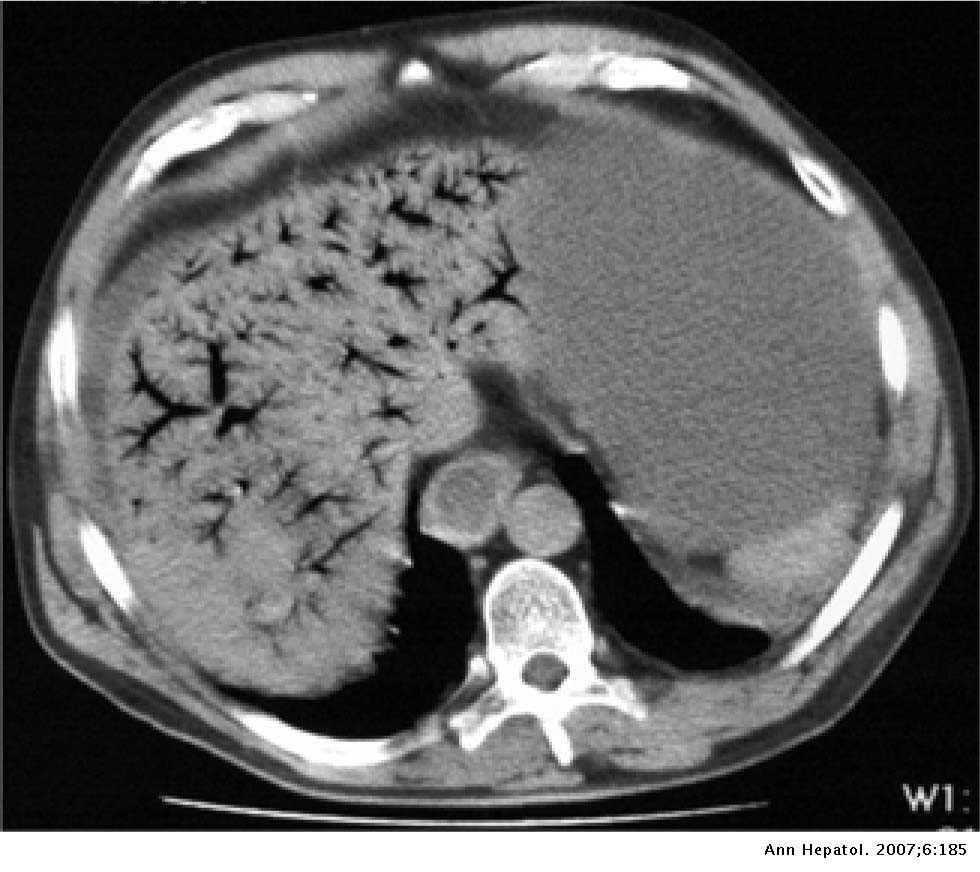

Hepatic portal venous gas Annals of Hepatology Source: elsevier.es